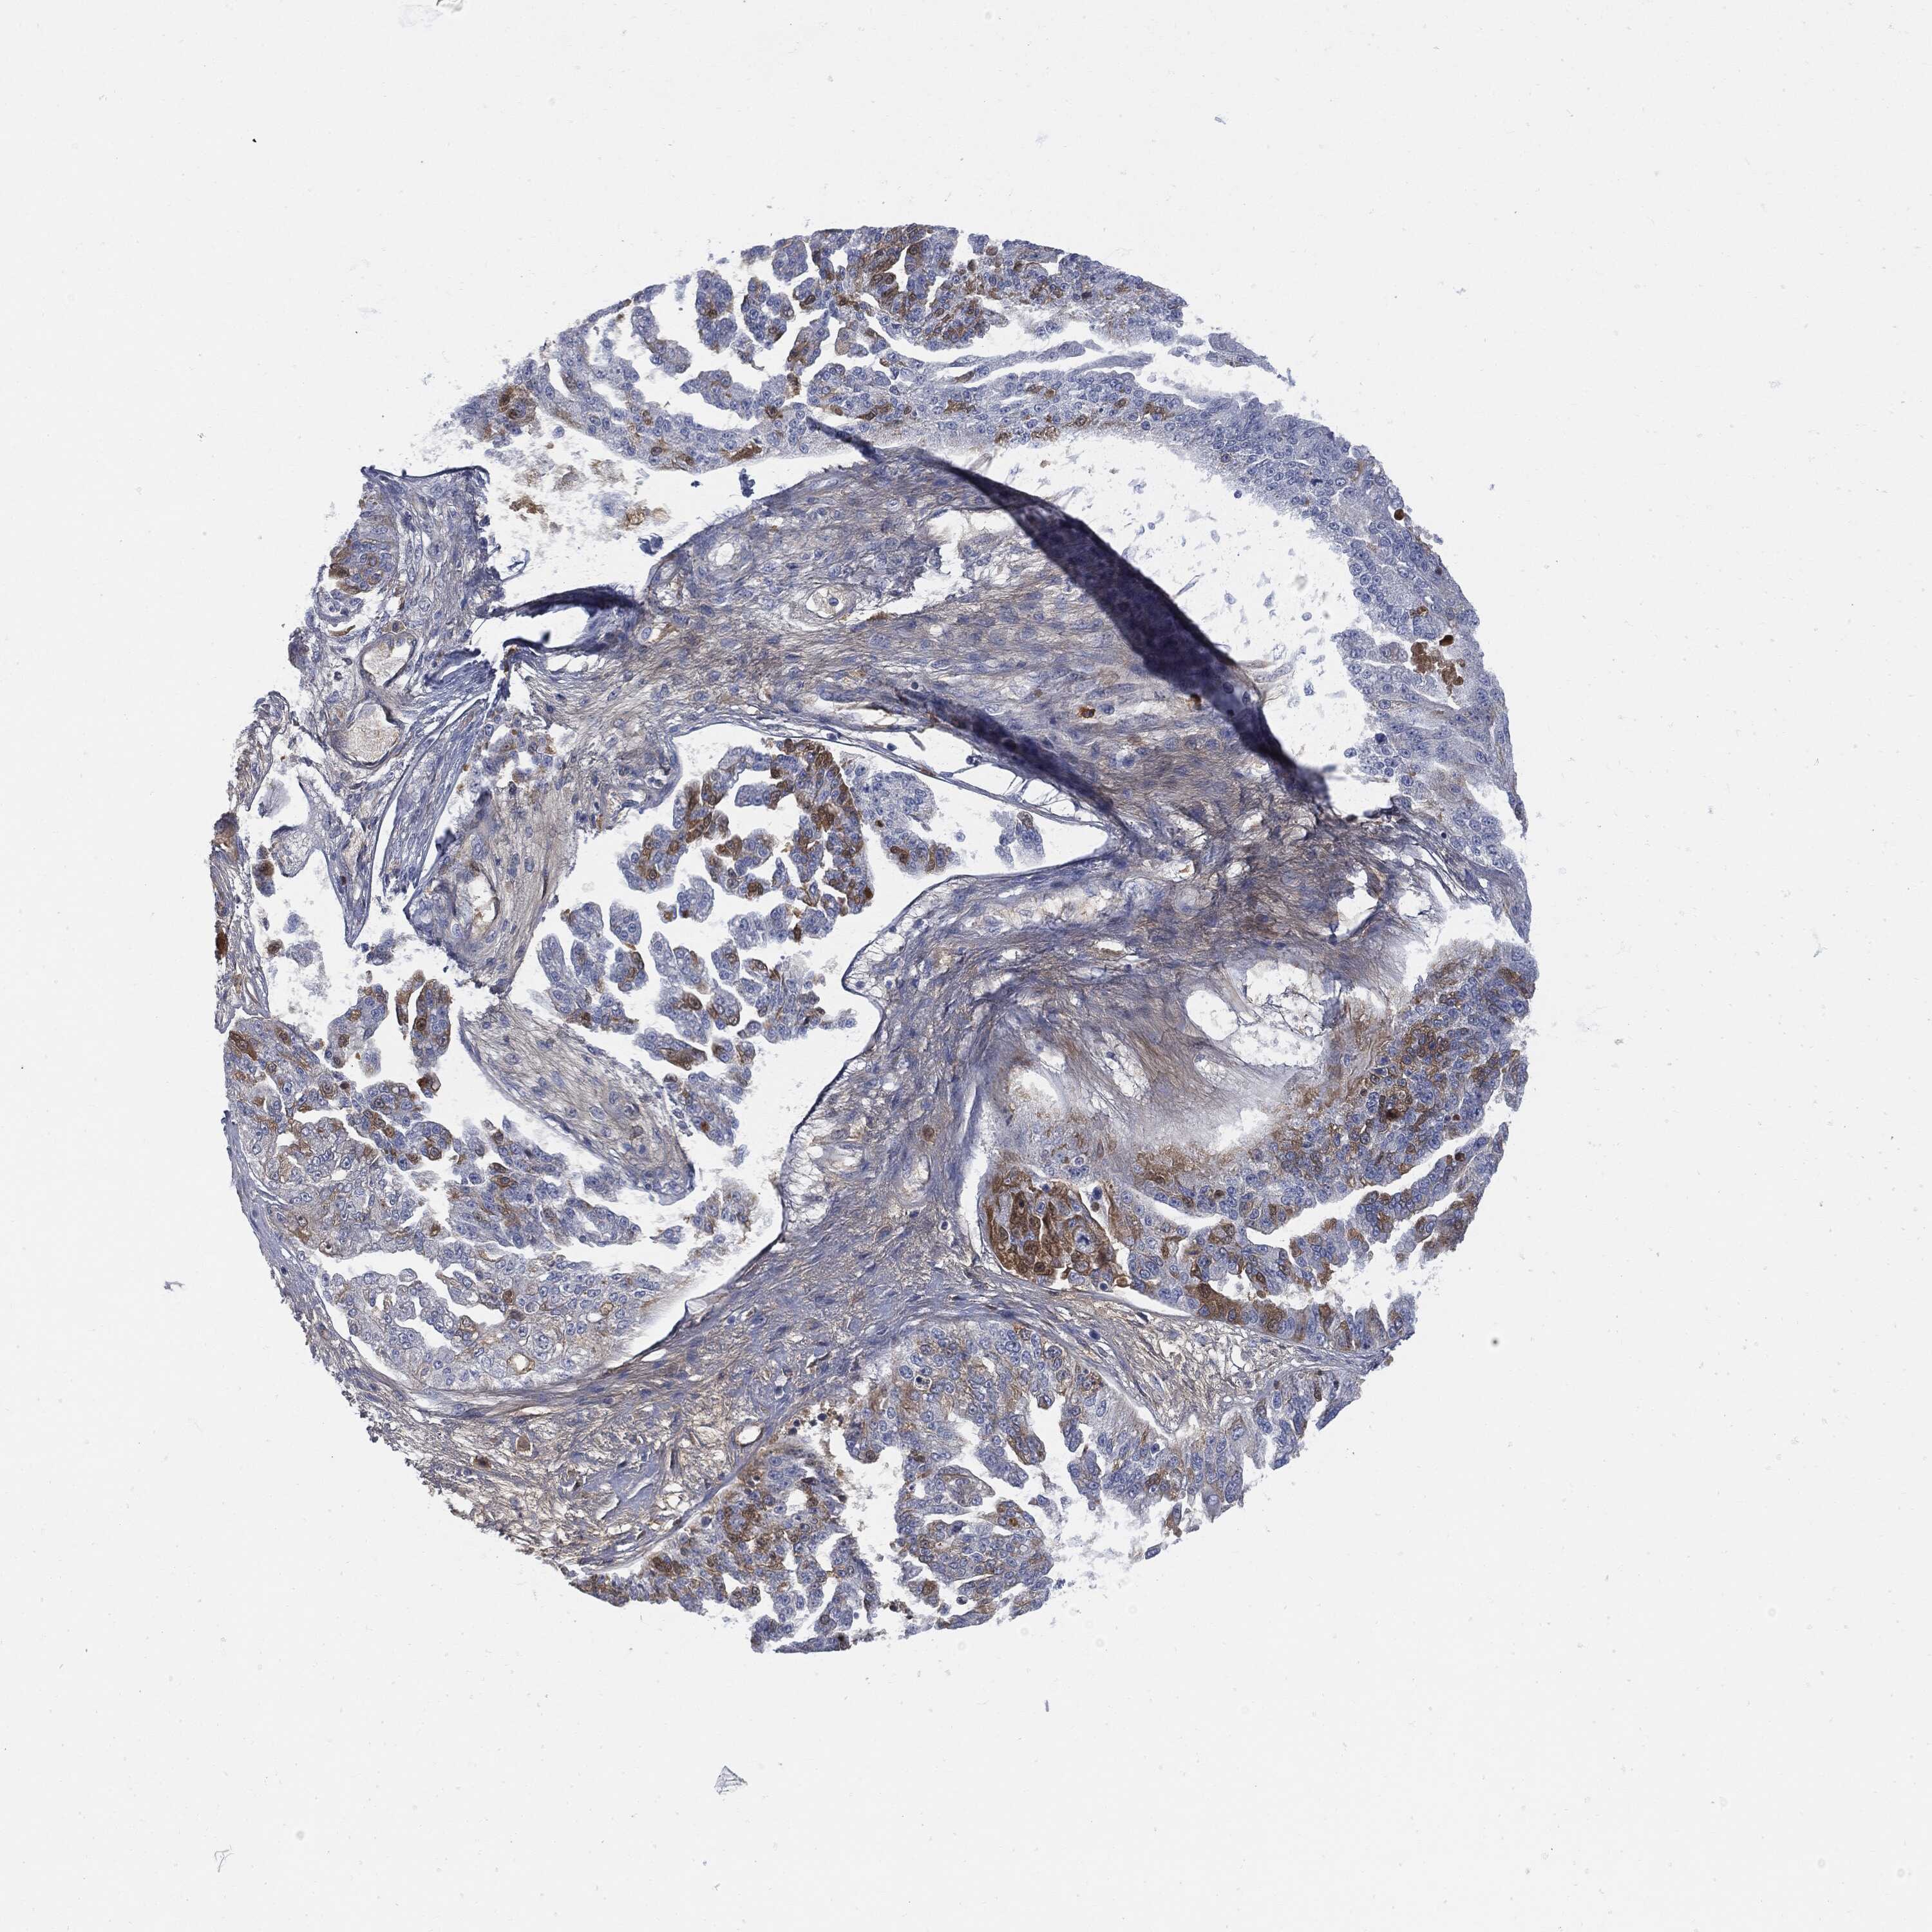

OVARIAN CANCER - Protein expressioni

A mouse-over function shows sample information and annotation data. Click on an image to view it in a full screen mode. Samples can be filtered based on level of antibody staining by selecting one or several of the following categories: high, medium, low and not detected. The assay and annotation is described here.

Note that samples used for immunohistochemistry by the Human Protein Atlas do not correspond to samples in the TCGA dataset.

Antibody stainingi

Antibody staining in the annotated cell types in the current human tissue is reported as not detected, low, medium, or high, based on conventional immunohistochemistry profiling in selected tissues. This score is based on the combination of the staining intensity and fraction of stained cells.

Each image is clickable and will lead to virtual microscopy that enables deeper exploration of all samples and also displays staining intensity scores, fraction scores and subcellular localization as well as patient and tissue information for each sample.

Antibody HPA001198

Antibody HPA002028

Antibody CAB016689

Antibody CAB080300

Cystadenocarcinoma, mucinous, NOS

Carcinoma, endometroid

Cystadenocarcinoma, serous, NOS

Carcinoma, NOS